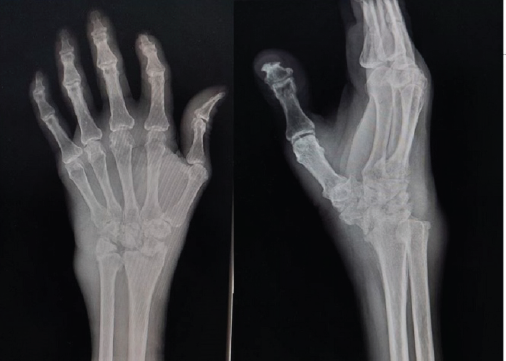

Charcot’s Arthropathy of the Wrist: A Case Report

V Ravi Kiran , Udit K Jayant , M L V Sai Krishna , Sanjay Singh Rawat , Tahir Ansari

………………………………p.148-152